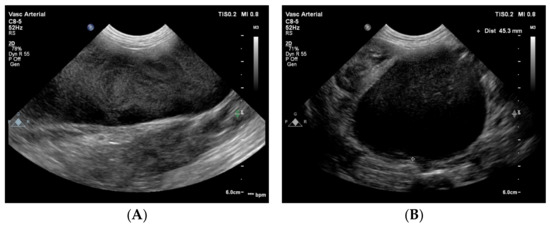

The CVC in the cranial abdomen showed an extreme aneurysm with a diameter up to 45 mm, with blood stasis to sluggish blood flow with spontaneous echo contrast in it (Figure 3). No thrombus was noted.

Figure 3. Two-dimensional grey-scale ultrasound images show an aneurysm of the azygos vein dorsal to the right kidney in longitudinal (A) and in cross section (B). In the vessel, spontaneous echo contrast is visible because of the blood stasis and sluggish flow. The images were obtained via the right lateral abdominal wall with the dog in left lateral recumbency. These findings suggest a severe venous obstruction downstream (i.e., cranial) to this location.